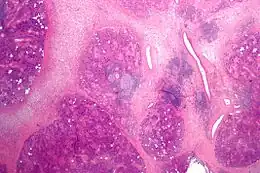

Coupe histologique de sialadénite chronique.